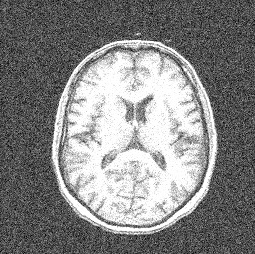

Figure 5 displays results obtained with the CNC, ATCG-TV, Chan & Vese, and LR-CNC algorithms for Gaussian noise level L=0.3L=0.3. These tests are applied to the MRI image with the cluster number set to K=3K=3, and to a Millennium simulation 222https://wwwmpa.mpa-garching.mpg.de/galform/virgo/millennium/ with cluster number K=2K=2.

Refer to caption Refer to caption Refer to caption Refer to caption Refer to caption Refer to caption

Original Observed Chan &\& Vese ATCG-TV CNC LR-CNC

Fig. 5: Segmented MRI and Millenium images for Gaussian noise with L=0.3L=0.3, and for K=3K=3 and K=2K=2, respectively.

Table 3 shows PSNR and SSIM values for segmented images determined by the CNC, ATCG-TV, Chan & Vese, and LR-CNC algorithms for several Gaussian noise levels LL when applied to the MRI and Millennium images. Figures 6 and 7 display the relative differences (38) and PSNR-values of images determined at each iteration of the CNC, ATCG-TV, and LR-CNC algorithms as functions of the iteration number when these algorithms are applied to the MRI and Millennium images. The Gaussian noise level is L=0.3L=0.3 and we seek to determine K=3K=3 and K=2K=2 clusters in the MRI and Millenium images, respectively.

method CNC ATCG-TV Chan &\& Vese [18] LR-CNC

LL PSNR SSIM PSNR SSIM PSNR SSIM PSNR SSIM

MRI 0.01 24.94 0.42 24.37 0.49 24.17 0.64 25.12 0.49

0.1 18.73 0.33 18.11 0.37 18.71 0.37 20.50 0.38

0.2 13.78 0.29 13.80 0.31 13.71 0.32 15.43 0.35

0.3 10.62 0.27 10.63 0.26 10.54 0.27 12.03 0.31

Millennium 0.01 22.74 0.71 22.40 0.69 18.94 0.37 22.40 0.69

0.1 18.14 0.62 16.20 0.30 16.66 0.30 20.30 0.65

0.2 13.34 0.49 12.21 0.26 13.09 0.24 18.29 0.59

0.3 10.10 0.40 9.15 0.22 10.11 0.20 13.60 0.51

Table 3: PSNR- and SSIM-values for images determined by the CNC, ATCG-TV, Chan & Vese, and LR-CNC algorithms for Gaussian noise with several noise levels LL.

Figure 5 shows the segmented images produced by the LR-CNC algorithm to retain details with high precision for both images, also when the amount of noise is large. Furthermore, the PSNR and SSIM values reported in Table 3 indicate that the LR-CNC algorithm consistently exhibits greater robustness than the other algorithm, with particularly strong performance for larger noise levels. Figures 6 and 7 illustrate the smooth and rapid convergence of the iterates determined by the LR-CNC algorithm.